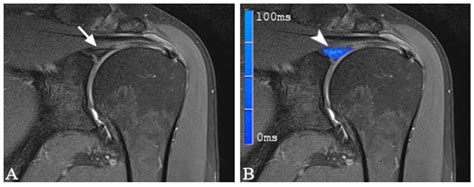

While a standard MRI is often the first step, it sometimes lacks the sensitivity needed to detect subtle tears in the labrum. This is where an MRI Arthrogram becomes necessary. An arthrogram involves injecting a contrast dye directly into the shoulder joint capsule before the MRI scan is performed. This contrast agent flows into the small crevices and tears within the labrum, effectively "lighting them up" on the resulting images.

• High Signal Intensity: The appearance of white or bright lines within the dark, triangular shape of the labrum, which indicates a separation or fluid collection.

• Paralabral Cysts: Small, fluid-filled sacs that often develop near the site of a chronic tear, acting as a secondary indicator of underlying labral damage.